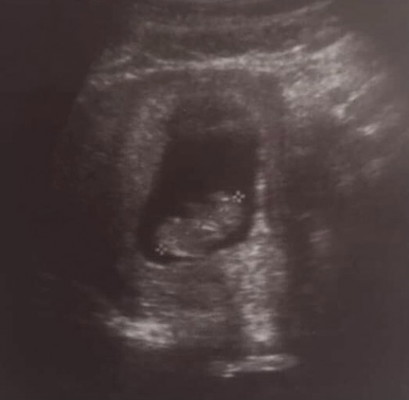

แม่ๆ ครรภ์ 9 w 6 d ถือว่าตัวเล็กไหมคะ

ขนาดของลูก2.95 cm แต่ตามประจำเดือนตอนอัลตร้าซาวน์ 10 weeks ค่ะ อยากทราบว่าดูยังไงคะอันไหนหัวอันไหนแขนอันไหนหน้าน้องคะ55555 ขอบคุณแม่ๆค้า